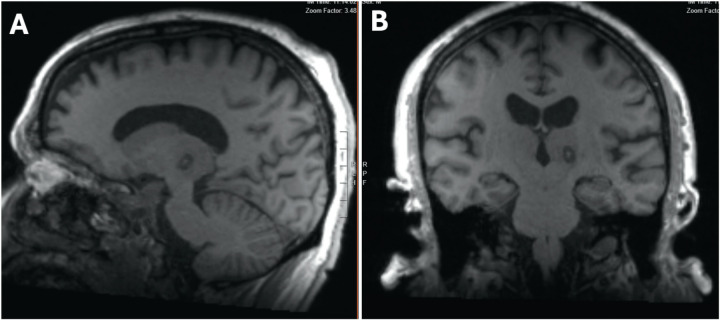

Material and methods: Preoperative and postoperative white matter null (WMn) MR-imaging was employed for direct Vim detection. Essential anatomical landmarks are identified. Dual-lesion conformality was used to adapt to the spatial distribution of the Vim.

Results: Lesions of the Vim were identifiable using the postoperative WMn MRI sequence. The direct visualization of the Vim usually avoids extension into the internal capsule and the sensory thalamic nucleus. Sagittal imaging confirmed the dual-lesion conformational strategy which conforms to the antero-superior orientation of the Vim.